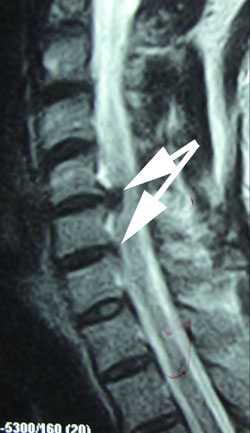

About A Juneau Contained Cervical Spine Disc Herniation

A thorough, clinical examination that may include imaging is important to your recovery.

In-office, Aurora Chiropractic Center uses Cox Technic Flexion Distraction and Decompression to lower the pressure in the disc so the nucleus pulposus returns to the center of the disc, aid in the healing of the torn anular fibers, and drive out chemicals that irritate and inflame the spinal nerves.